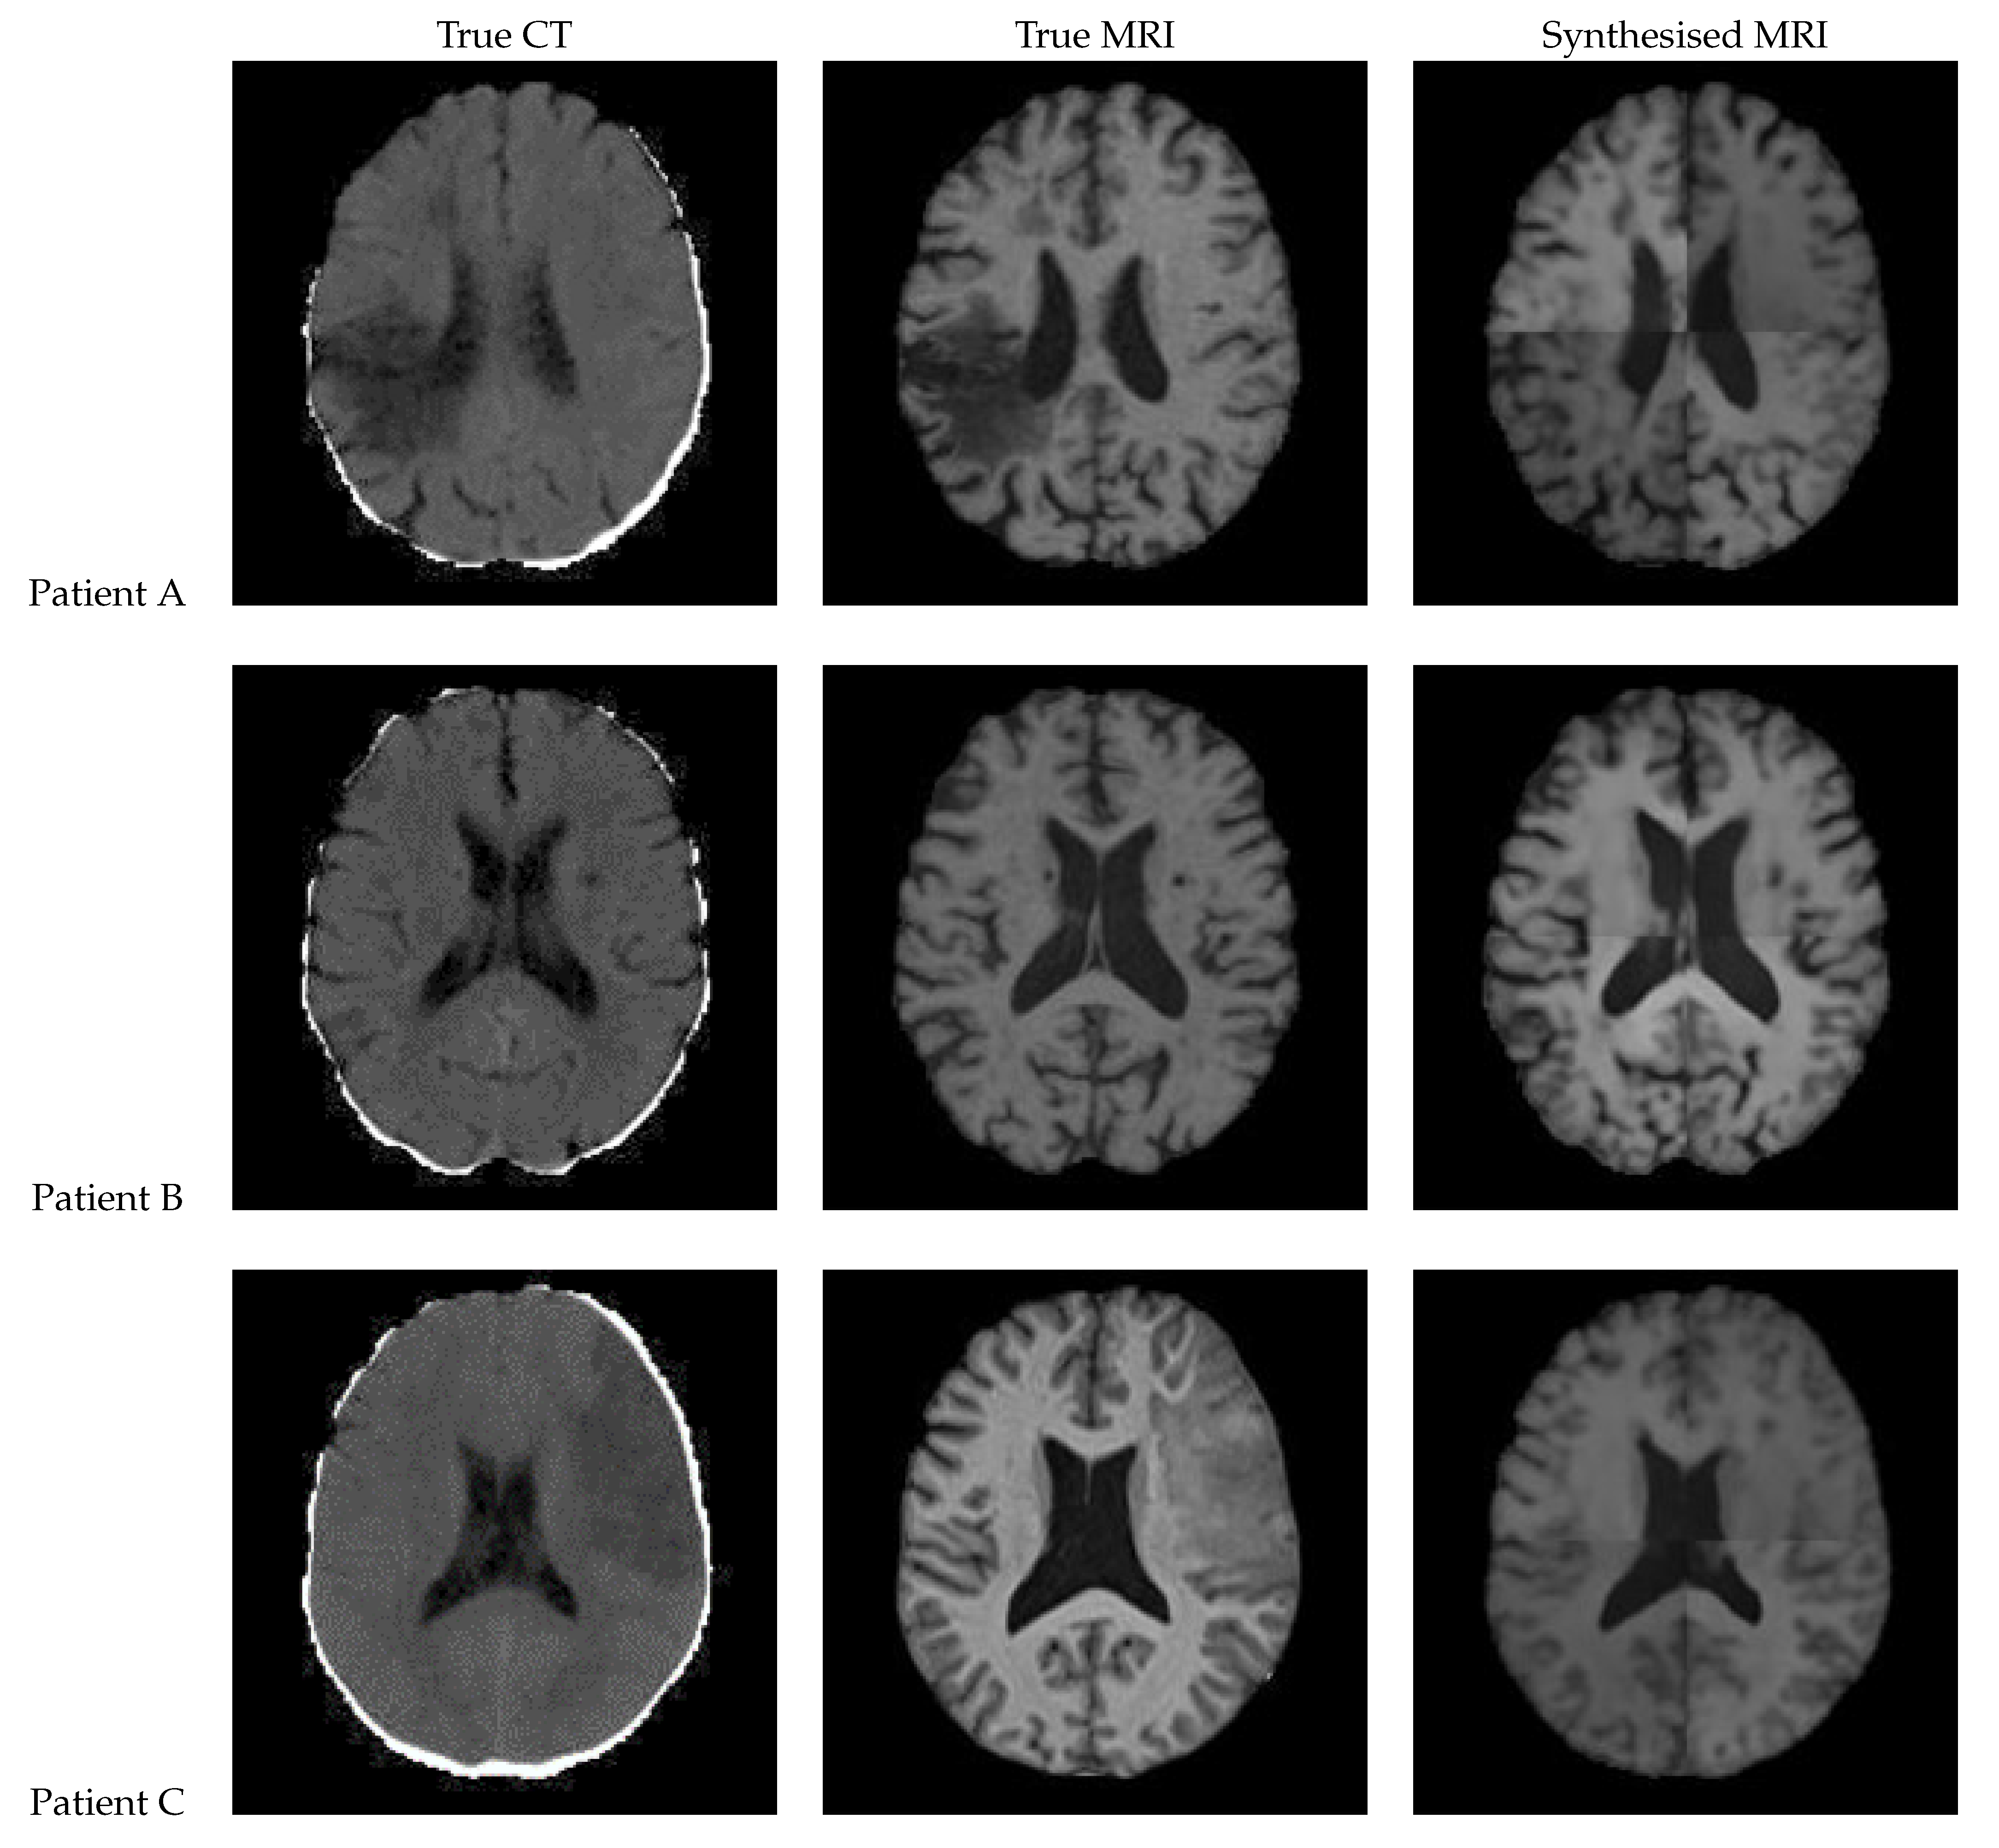

Figure 12 shows a sample slice of the synthetic MRI generated by a 3D UNet for three patients in the test set, along with the corresponding true MRI and CT slices. Patient A presents a large lesion, which can also be seen in the synthesised MRI, but with reduced contrast and less precise borders. Patient B shows a similar overall contrast to the true MRI. Patient C displays a very large, faint lesion that is not clearly visible in the synthetic MRI.

Figure 12. Axial slices of CT Scans (Left), True MRIs (Centre), and Synthetic MRIs generated by UNet (Right).

True CT True MRI Synthesised MRI

Patient A

Patient B

Patient C